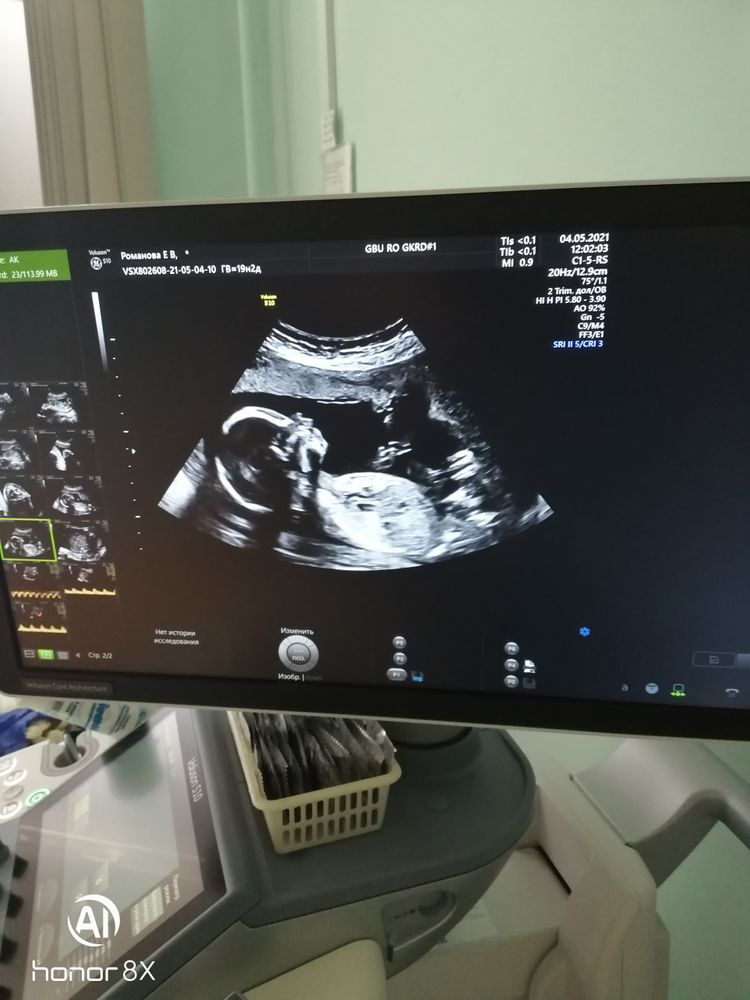

Но мы и это пережили, второй скрининг хороший🙏сынулька в норме-вес 300гр,вод норма, плацента норма,глазки, носик, животик, ножки, ручки-пальчики на месте все симметрично😍чсс-150уд. Малыш сначало спал, врач начала давить датчиком на живот он проснулся, начал выгибаться вертеть головой и дрыгать ножками и даже видно было как открывал ротик, ручками трогал личико😍это так здорово все наблюдать-прям человек на экране в отличии даже от первого узи-скрининга! сегодня нам ровно 20 неделек по узи🤗

Спасибо вселенной за то что сынок здоровый, больше ничего не нужно🙏🙏🙏я счастлива🙈